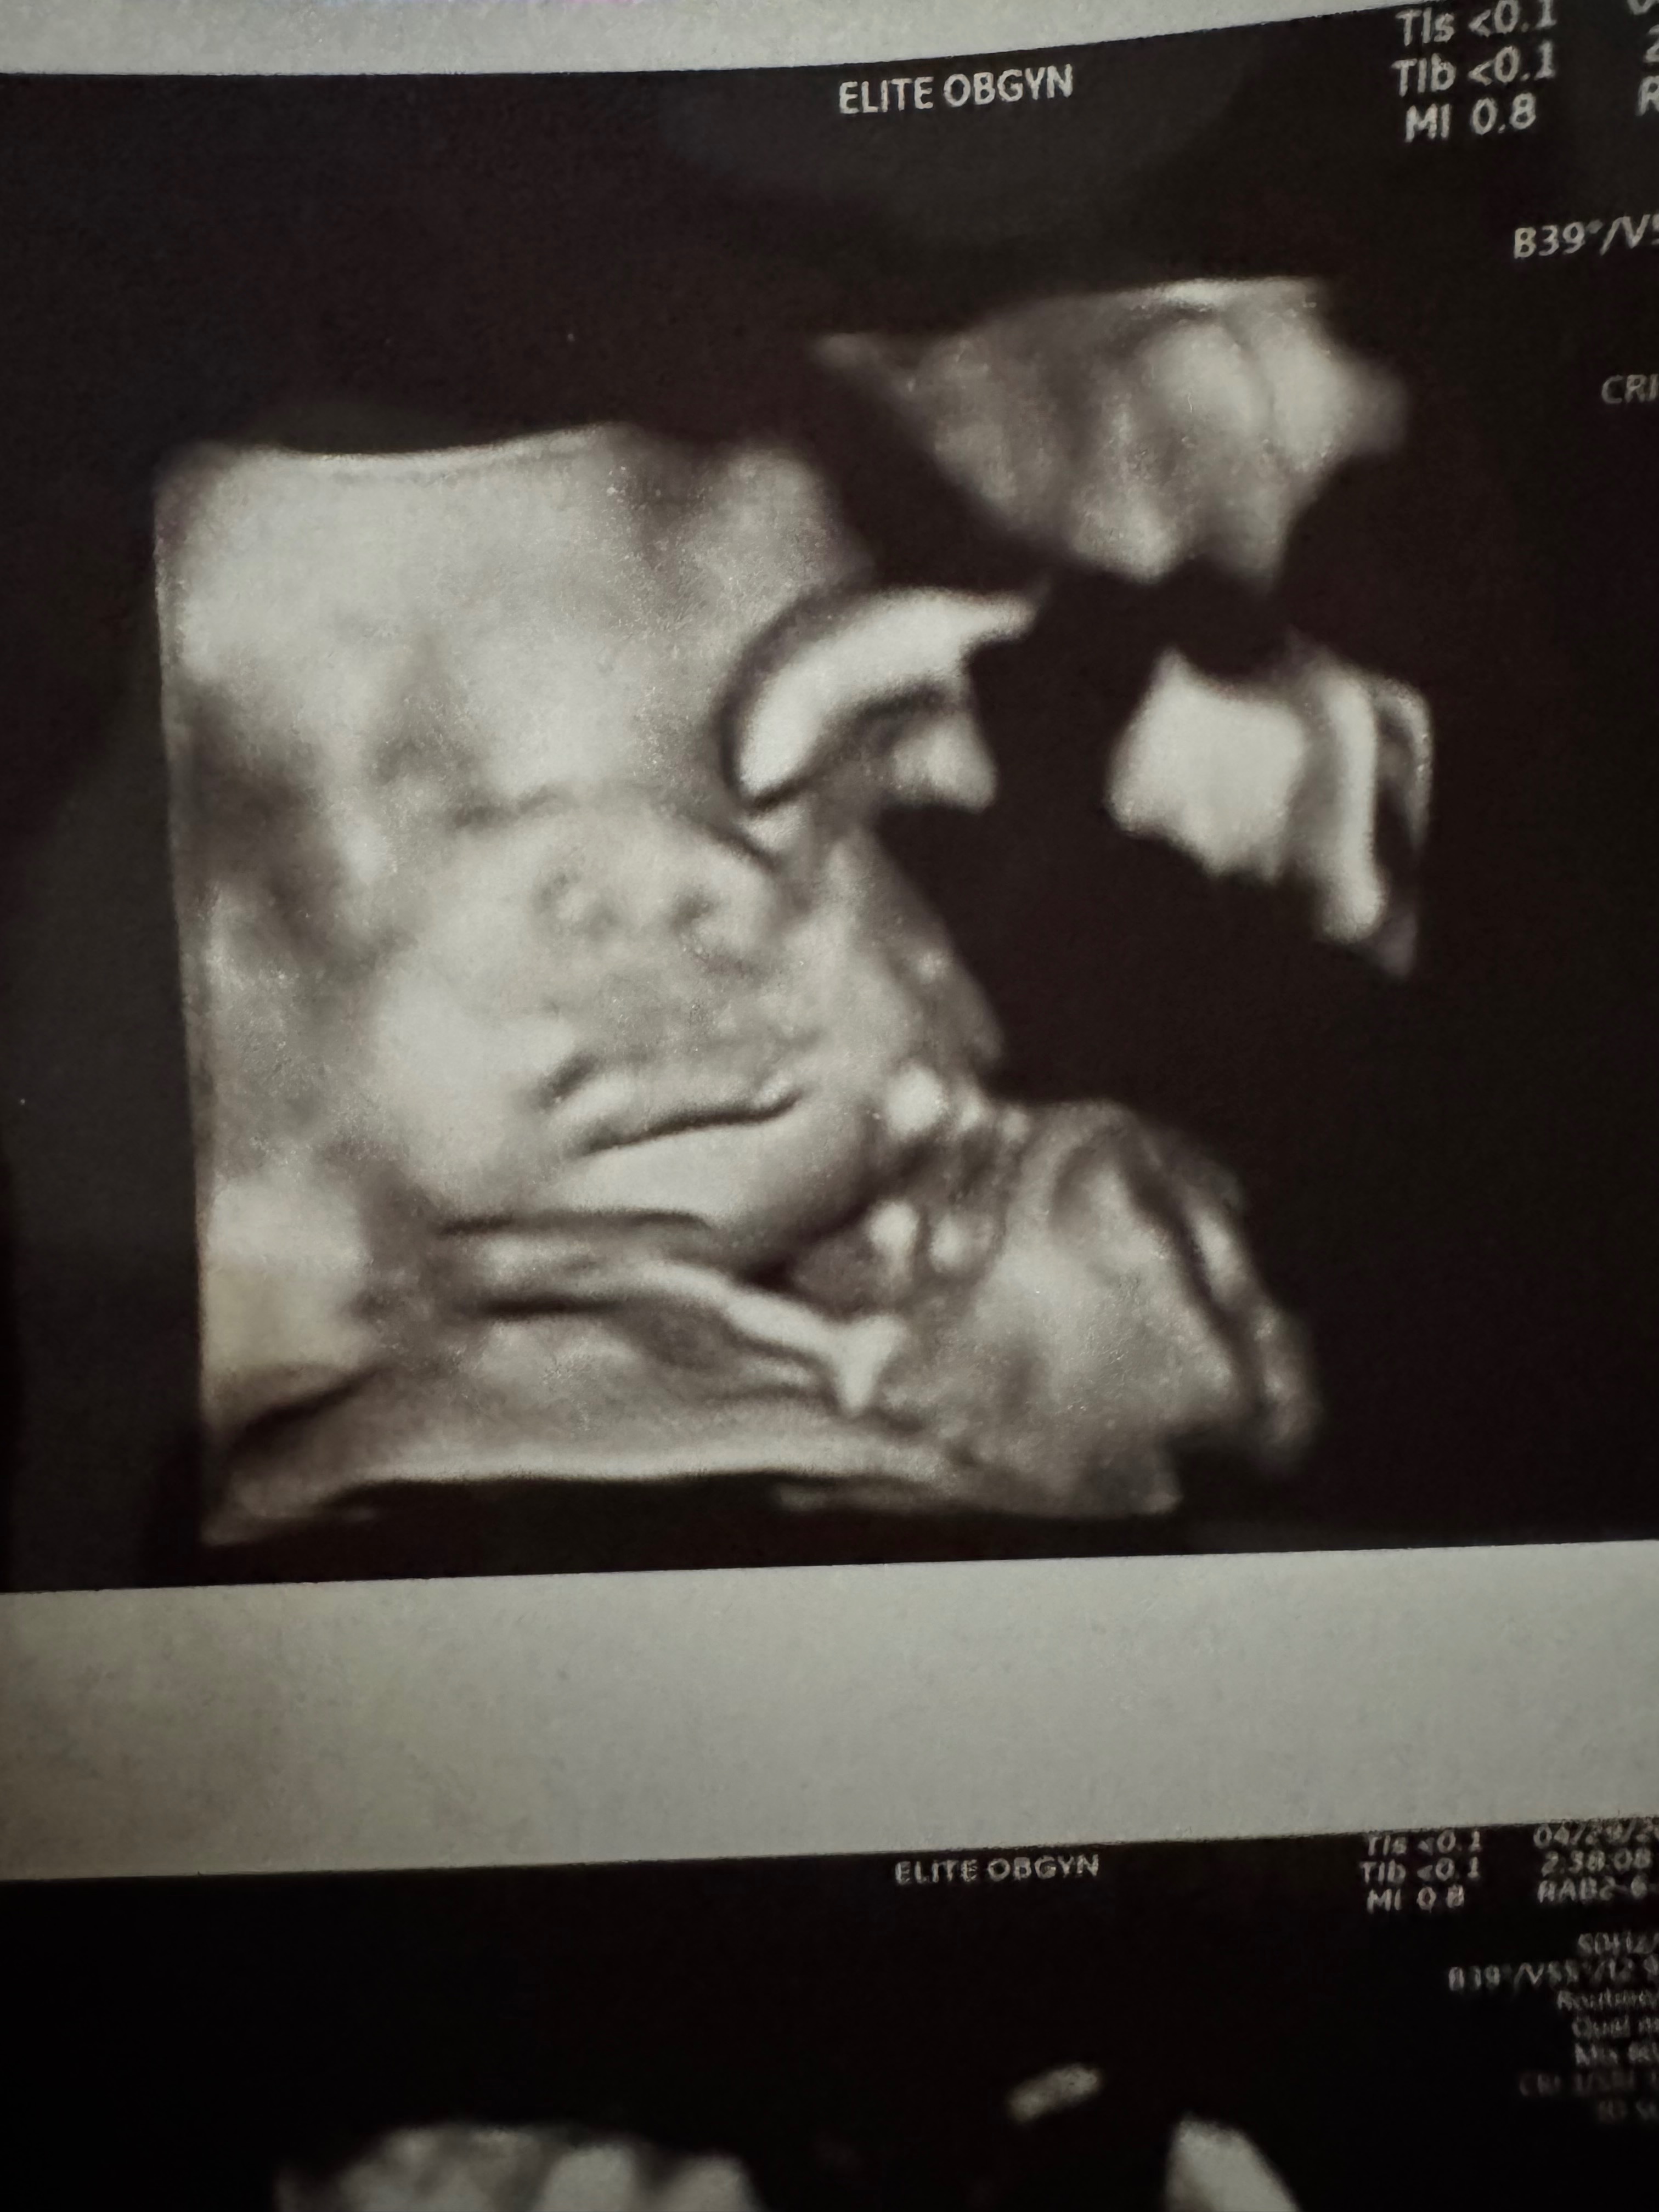

I need everyone to share my story and support my go fund me . On June 9th I went in for a ultra sound at 37 weeks. By June 13th I was being rushed to the hospital. Because my baby was no longer moving. His death was caused due to the umbilical cord wrapped around his neck. A 3d ultra sound was never performed. I know my baby would still be here if the doctor had. Done the proper procedures.